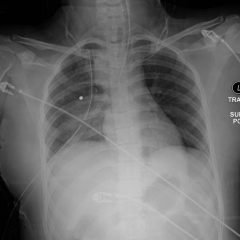

Hemothorax Pre and Post Chest Tube CXR